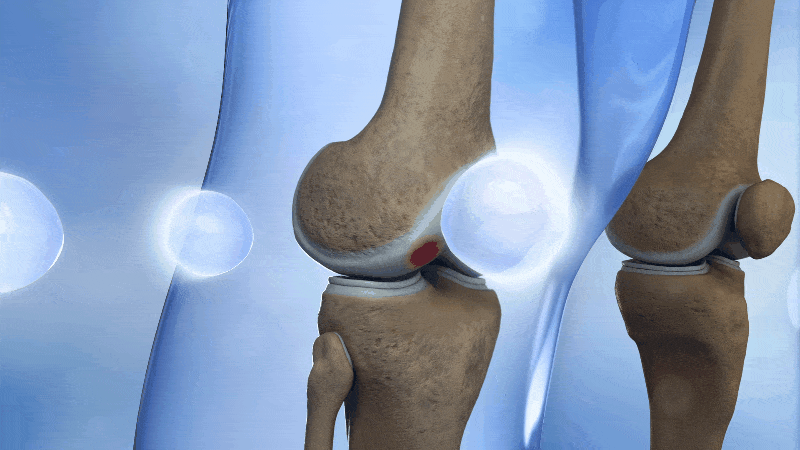

Doctors are trained to look at structure. They see a scan that shows thinning cartilage, a torn meniscus, or a bulging disc…and immediately assume that’s the cause of your pain.

But your joints are much more complicated than what shows up on an MRI.

Cartilage doesn’t have nerves, so it can’t actually feel pain. That ache, stiffness, and swelling you’re feeling is coming from the tissues around it: the bones, muscles, joint capsule, bursae, ligaments, tendons and all the pressure that is caused by the swelling and inflammation in the area.

This is the part most doctors miss.